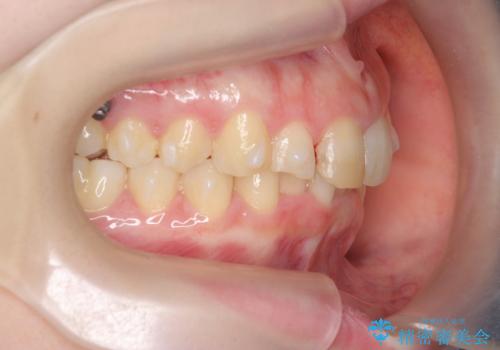

前歯のがたつき 深い噛み合わせを改善したい

- 「前歯のガタつきをきれいにしたい、噛んだ時に下の前歯が見えないことを改善したい」とマウスピース矯正を希望され来院されました。

マウスピースに加え、矯正用マイクロインプラントやゴムを併用し、がたつきや噛み合わせの深さを改善していきます。

ゴムかけやマウスピースの装用時間、しっかりとマウスピースをはめ込むチューウィーをしっかりと使用したことで良好な治療結果を得ることができました。